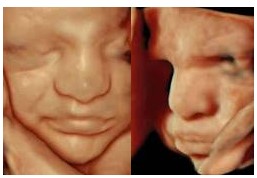

Fetus mit 31 Schwangerschaftswochen: Erst lächelt das Ungeborene etwas, wenige Minuten später zeigt es ein missmutiges Gesicht. (Quelle: Prof. E. Merz)

Wenn Ärzte ein Ungeborenes mit 4D-Ultraschall untersuchen, schließen sie dabei nicht nur mögliche Fehlbildungen aus. Sie können auch live beobachten, wie das Kind Körper und Gesicht bewegt. „Mit der 4D-Sonografie, die Bewegungen des Feten räumlich sichtbar macht, können wir die Mimik des Kindes besonders gut beobachten“, sagt Professor Dr. med. Eberhard Merz, Leiter des Zentrums für Ultraschall und Pränatalmedizin am Krankenhaus Nordwest in Frankfurt. Die Technik ermöglicht es den Ärzten heute auch, das Farbspektrum der menschlichen Haut anzupassen und mit einer beweglichen virtuellen Lichtquelle Effekte von Licht und Schatten an der Oberfläche des Kindes zu erzeugen. „Die Bilder erscheinen sehr lebensecht und es ist kein Wunder, dass sie uns innerlich berühren“, so DEGUM-Experte Merz. Dennoch bedeute ein Lächeln nicht, dass ein Baby glücklich ist und eine traurige Mine verrate nichts über schlechte Gefühle des Ungeborenen.